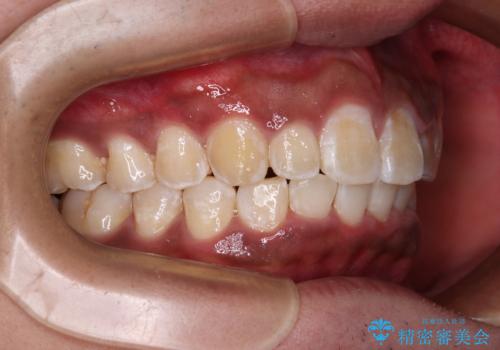

- 深く咬みこみ、前に飛び出した上顎前歯を気にして来院された患者様です。

口元の突出感はあまりありませんでしたが、上顎歯列が全体的に前方にあり、更には下顎歯列が深く咬みこんでいるために、上顎前歯が前方に突出している状態でした。